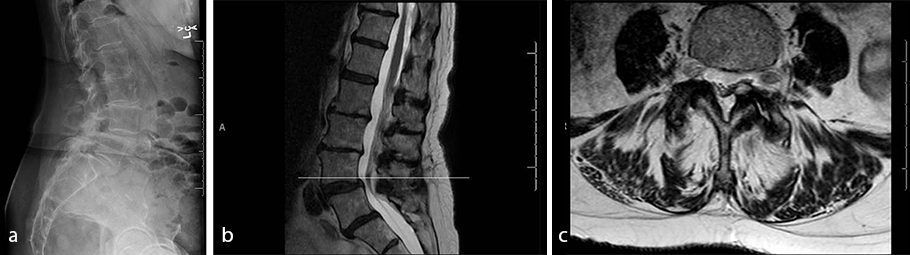

- Imaging revealed L4/L5 spondylolisthesis and a left-sided synovial cyst (Fig 8)

- Diagnosis: lumbar spondylolisthesis and radiculopathy